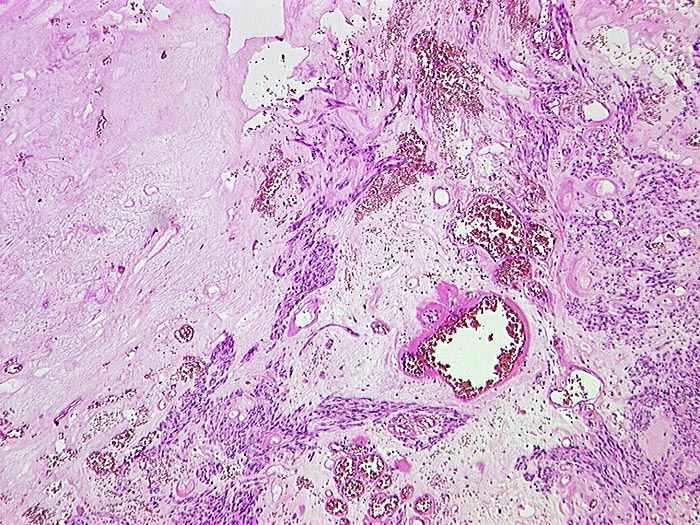

Makroskopisch imponieren kleine Tumoren als peritoneale, intramurale oder submuköse Knoten. Grössere Tumoren wölben sich oft vor und können ulzerieren. Die Schnittfläche ist weisslich und kann Einblutungen, Zysten, Fibroseareale oder Nekrosen aufweisen. Histologisch werden Spindelzelltyp (70%), Epitheloidzelltyp (20%) oder gemischtzelliger Typ (10%) unterschieden. Der histologische Subtyp scheint keinen Zusammenhang mit zugrundeliegender Mutation, Therapieansprechen und Prognose zu haben. Gelegentlich sind vor allem die kleineren Tumoren zellarm und kollagenreich.

• Scharf begrenzter kugeliger Tumor in der Submukosa des Magenantrums

• Der Tumor besteht aus längs und quer getroffenen Faszikeln spindelförmiger Tumorzellen, welche an glatte Muskelzellen oder Schwannzellen erinnern.

• Herdförmig pseudozystische Auflockerung des Tumorgewebes.